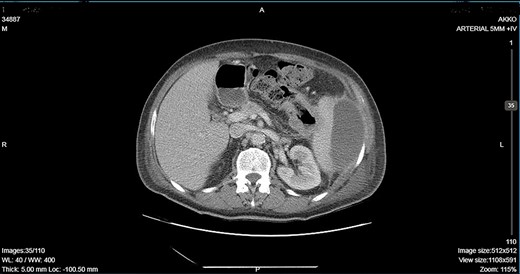

CT showing an important decrease of the abscess due to its rupture toward the peritoneal cavity and presence of air in the abdominal cavity.

A 64-year-old man presented to the emergency department with left pleuritic chest pain, anorexia and fever with rigors. His vital signs included a pulse of 130 beats/min, blood pressure of 108/51 mmHg, respiratory rate of 18 breaths/min, oxygen saturation of 95% and body temperature of 36.1°C. He had no relevant medical history. The patient was admitted to the hospital with the diagnosis of pneumonia based on his chest X-ray findings. The patient remained hemodynamically stable through the next day but developed a temperature of 39.2°C. A CT scan revealed a tumor of the splenic flexure that had invaded the spleen and pancreas via the transcoelomic route and created a subcapsular splenic abscess (Fig. 1). The CT scan also revealed splenic vein thrombosis located proximal to the tail of the pancreas. CT-guided percutaneous drainage of the abscess was scheduled for the following day. The patient’s clinical condition suddenly deteriorated and he became hemodynamically unstable. Abdominal distention with diffuse tenderness was identified via clinical examination, and laboratory tests revealed leukocytosis with a white blood cell count of 16.800/mm and anemia, with a hematocrit of 28.5%. An emergent CT scan revealed intraperitoneal rupture of the splenic abscess (Fig. 2). Intraoperative findings of an urgent surgical intervention included severe, diffuse purulent peritonitis with a large amount of pus mixed with blood clots in the peritoneal cavity that required cautious cleaning and thorough lavage. Furthermore, a large, hard, immovable tumor was identified in the splenic flexure of the colon. The tumor was tightly adherent to the spleen; we also noted the presence of intense inflammation and local fibrosis that extended to the surrounding tissues. En-block splenectomy and a wide left colectomy were performed followed by closure of the distant colon remnant using a linear stapler; furthermore, we also created an ostomy of the proximal colon remnant, similar to Hartmann’s procedure and drained the abdominal cavity. Transfusion of 600 ml of red blood cells was required. Extubation and postoperative recovery were uneventful, and the patient’s clinical status and parameters remained stable. Antibiotic treatment included meropenem 2 g thrice daily, metronidazole 500 mg thrice daily and amikasin 1 g once daily. The postoperative course was uneventful and the patient was discharged on postoperative day 12. Histopathological examination of the resected specimen revealed a 6 cm diameter perforated tumor adherent to an 18 × 13 × 6 cm spleen and a moderately differentiated grade 2 adenocarcinoma with infiltration to the pericolic fat. The resection margins were free of infiltration as were all of the 19 resected lymph nodes. A metastatic tumor, 2 cm in diameter, was identified in the spleen portal. The TNM stage was T3N0M1a (stage IVA disease), and the patient was referred to the Oncologic Department for adjuvant chemotherapy. He was administered eight cycles of Capecitabine that is changed into 5-fluorouracile + Oxaliplatin along with the necessary follow-up care. The patient has been disease-free for 2 years after the treatment.